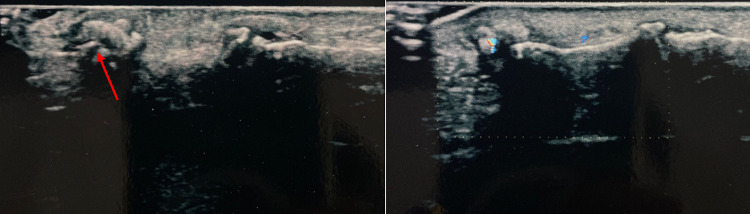

Fig. 2.

Case 2. A 25-year-old man was admitted to our hospital with a splinter of glass in the subcutaneous area of the palmar surface of the right hand. The splinter was barely visible on US grayscale as a small plaque of about 4 mm maximum size. In this case TA confirmed the presence and location of the FB